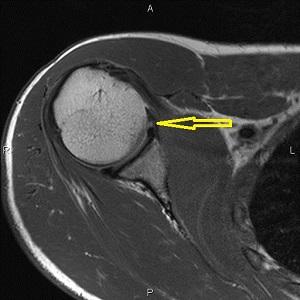

Повреждение банкарта плечевого сустава на МРТ свидетельствует о том, что основной причиной проблемы является отрыв хрящевой дуги (суставной губы) от костной ткани (лопатки).

Диагностика осуществляется с помощью рентгенографии, магнитно-резонансной томографии и компьютерной томографии. Эти методы позволяют определить локализацию и степень разрыва банкарта.